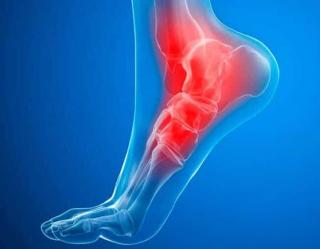

Боль в голеностопном суставе — частая жалоба как у спортсменов, так и у людей, ведущих обычный образ жизни. Даже незначительная травма может вызвать воспаление, ограничить подвижность и привести к хроническим изменениям, если вовремя не обратиться к врачу. При появлении боли, отёка, хруста или ощущения нестабильности необходимо записаться на приём к травматологу.

Чаще всего боль возникает после травм, переохлаждения, чрезмерной нагрузки или ношения неудобной обуви. Среди наиболее распространённых причин:

• растяжения и разрывы связок;

• ушибы, переломы лодыжек;

• воспалительные процессы — артрит, тендинит;

• дегенеративные заболевания — артроз, остеохондропатии;

• последствия старых травм или неправильного срастания костей.